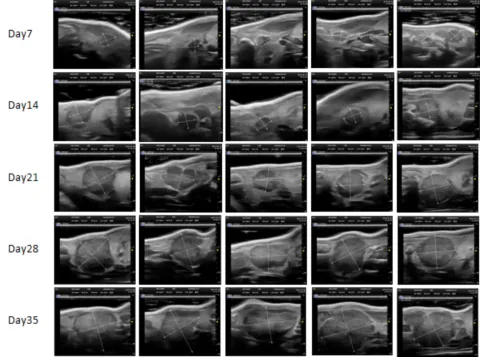

PDX Model (Growth Curve)

部分HJC黄金城平台PDX原位模型展示